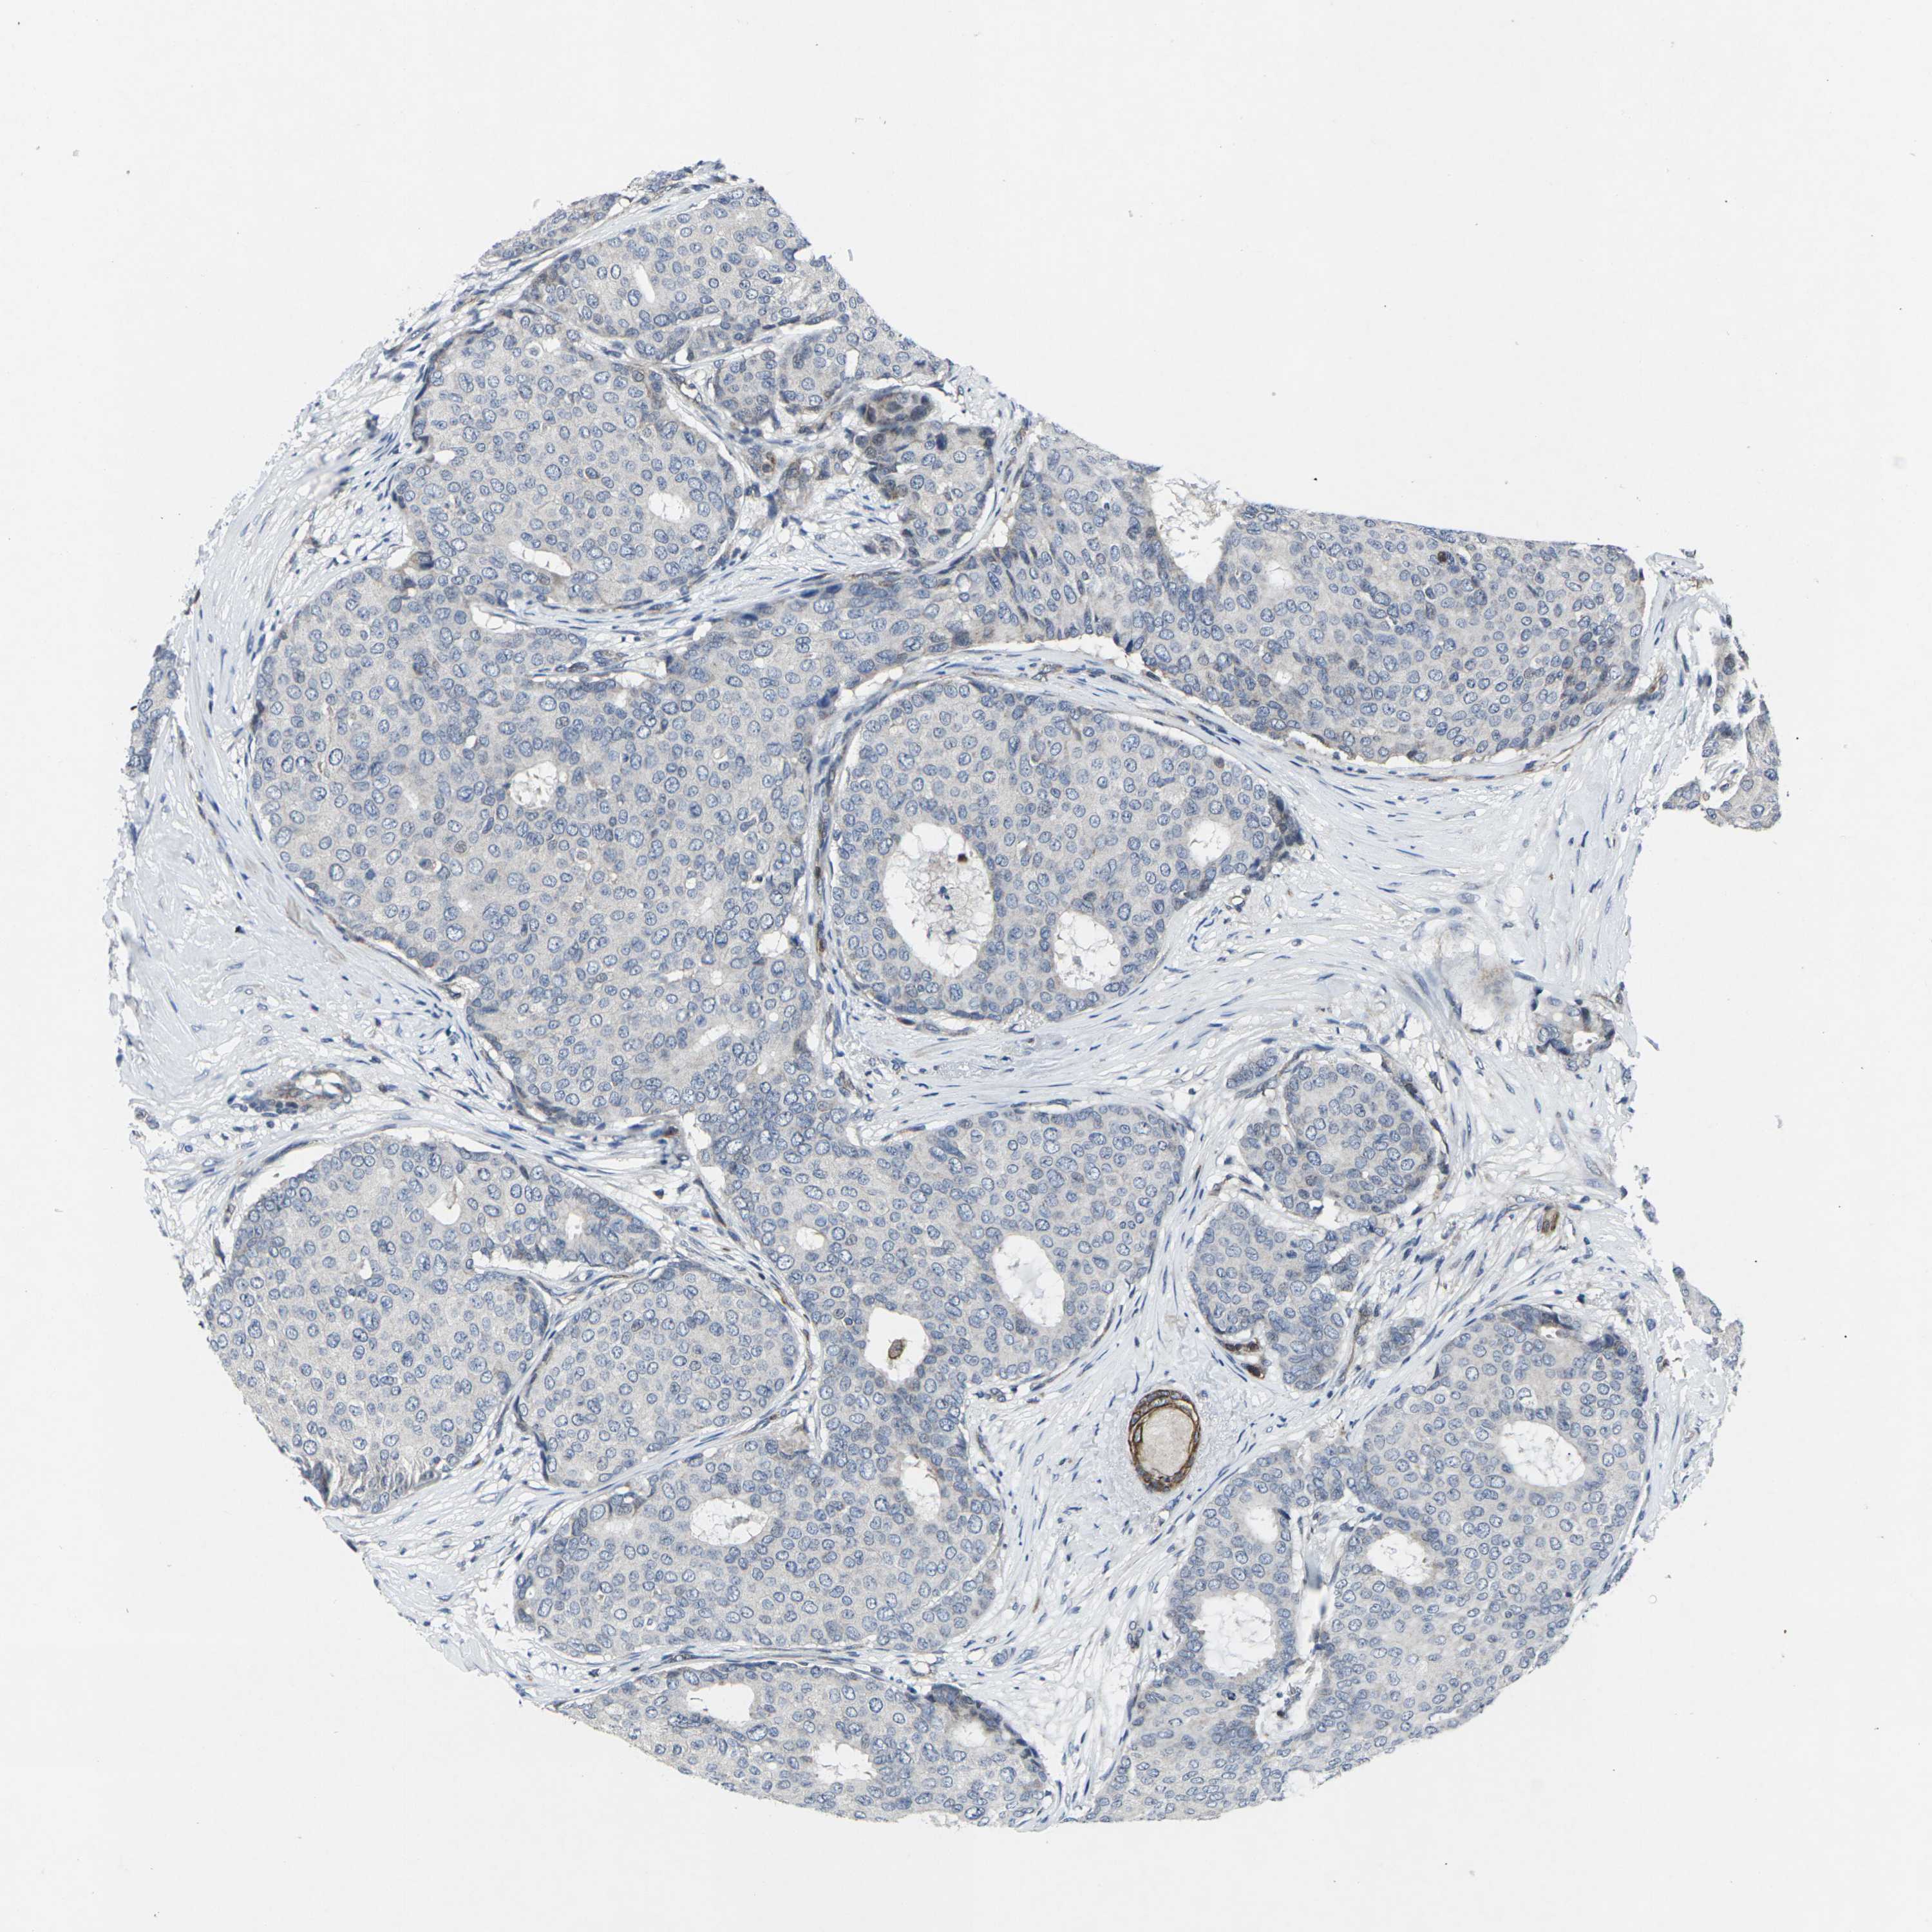

CANCER BREAST CANCER Show tissue menu

BRCA TCGA BRCA VALIDATION PROTEIN EXPRESSION